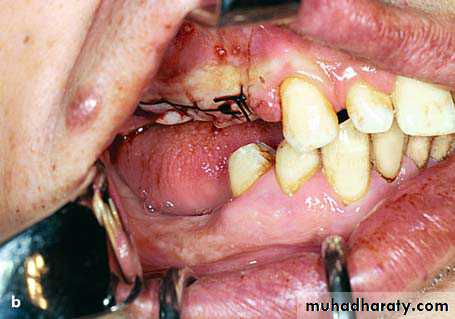

Torus Mandibularis

Torus mandibularis is an exostosis of unknown etiology.

It is localized in the lingual aspect of the body of the mandible, either on one side or more commonly on both sides (canine & premolar region).

Clinically, it is an asymptomatic bony protuberance covered by normal mucosa. Radiographically, it presents as a circumscribed radiopacity in the area of localization.

Torus mandibularis is completely innocent in nature and does not require any therapy whatsoever, except in cases where complete dentures are to be constructed.

preprosthatic surgery